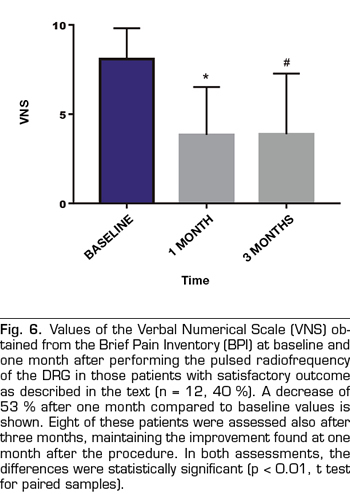

Results: The VNS score decreased from 7.7 ± 2,2 to 5.9 ± 3 (p < 0.01). Intensity and Interference Scores were reduced from 7.1 ± 1.5 to 5.9 ± 2.1 (p < 0.01) and 7.1 ± 1.9 to 6.0 ± 2.3 (p < 0.02) respectively. In 12 patients (40 %) a satisfactory analgesic response was observed. In these patients the VNS decreased from 8.0 ± 1.5 to 3.8 ± 2.6. Intensity and Interference Scores were reduced from 7.4 ± 1.3 to 3.9 ± 1.5 (p < 0.0001) y 7.7 ± 1.9 to 4.9 ± 2,7 (p = 0.002) respectively.

The score in the VNS prior to the procedure was reduced from 7.7 ± 2.2 to 5.9 ± 3 (p <0.01, t test for paired samples), taking into account the entire sample (n = 30), which implies a variation of 23% (Table I, Figure 3). The Intensity Index decreased from 7.1 ± 1.5 to 5.9 ± 2.1 (p <0.01), which implies a change of 16%, while the Interference Index decreased by 15% (7.1 ± 1.9 to 6.0 ± 2.3) (p <0.02) (Table I, Figures 4 and 5). When evaluating the patients who responded favorably using VNS, 12 out of 30 patients showed a decrease of at least 2 points on that scale, representing 40% of the sample. If we analyze these patients separately, we can observe that the initial values of VNS decreased from 8.0 ± 1.5 to 3.8 ± 2.6 after the procedure, which implies a reduction of 53% (Table II, Figure 6).

In eight patients with a satisfactory outcome after one month, a three-month evaluation of the procedures was conducted. In these, the VNS remained at low values, 3.8 ± 3.3 (p = 0.007), something similar happened with the Intensity and Interference Indexes, being 4.3 ± 1.6 and 5.4 ± 2.5, respectively (p = 0.001 and p = 0.02, when compared with the baseline values (Figures 6, 7 and 8).